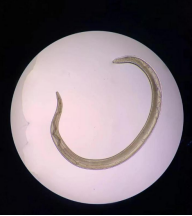

这些虫子在眼睛里是游动状态,十分灵活,一碰就游走,每条长约1厘米到2厘米不等,跟缝衣线一样粗细!

经医院检验科化验得知,这种虫子是一种寄生虫,叫做结膜吸吮线虫。为什么寄生虫会跑进豆豆的眼睛里?

结膜吸吮线虫,虫体细长、半透明、淡红色,离开宿主之后变成乳白色。